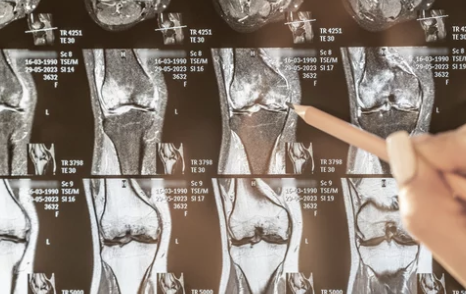

| MRI 검사 | 연골 손상, 인대 파열, 관절 내 염증 확인 |

- 무릎 관절염과 연골 손상 여부를 구별하기 위해 MRI 검사가 효과적입니다.